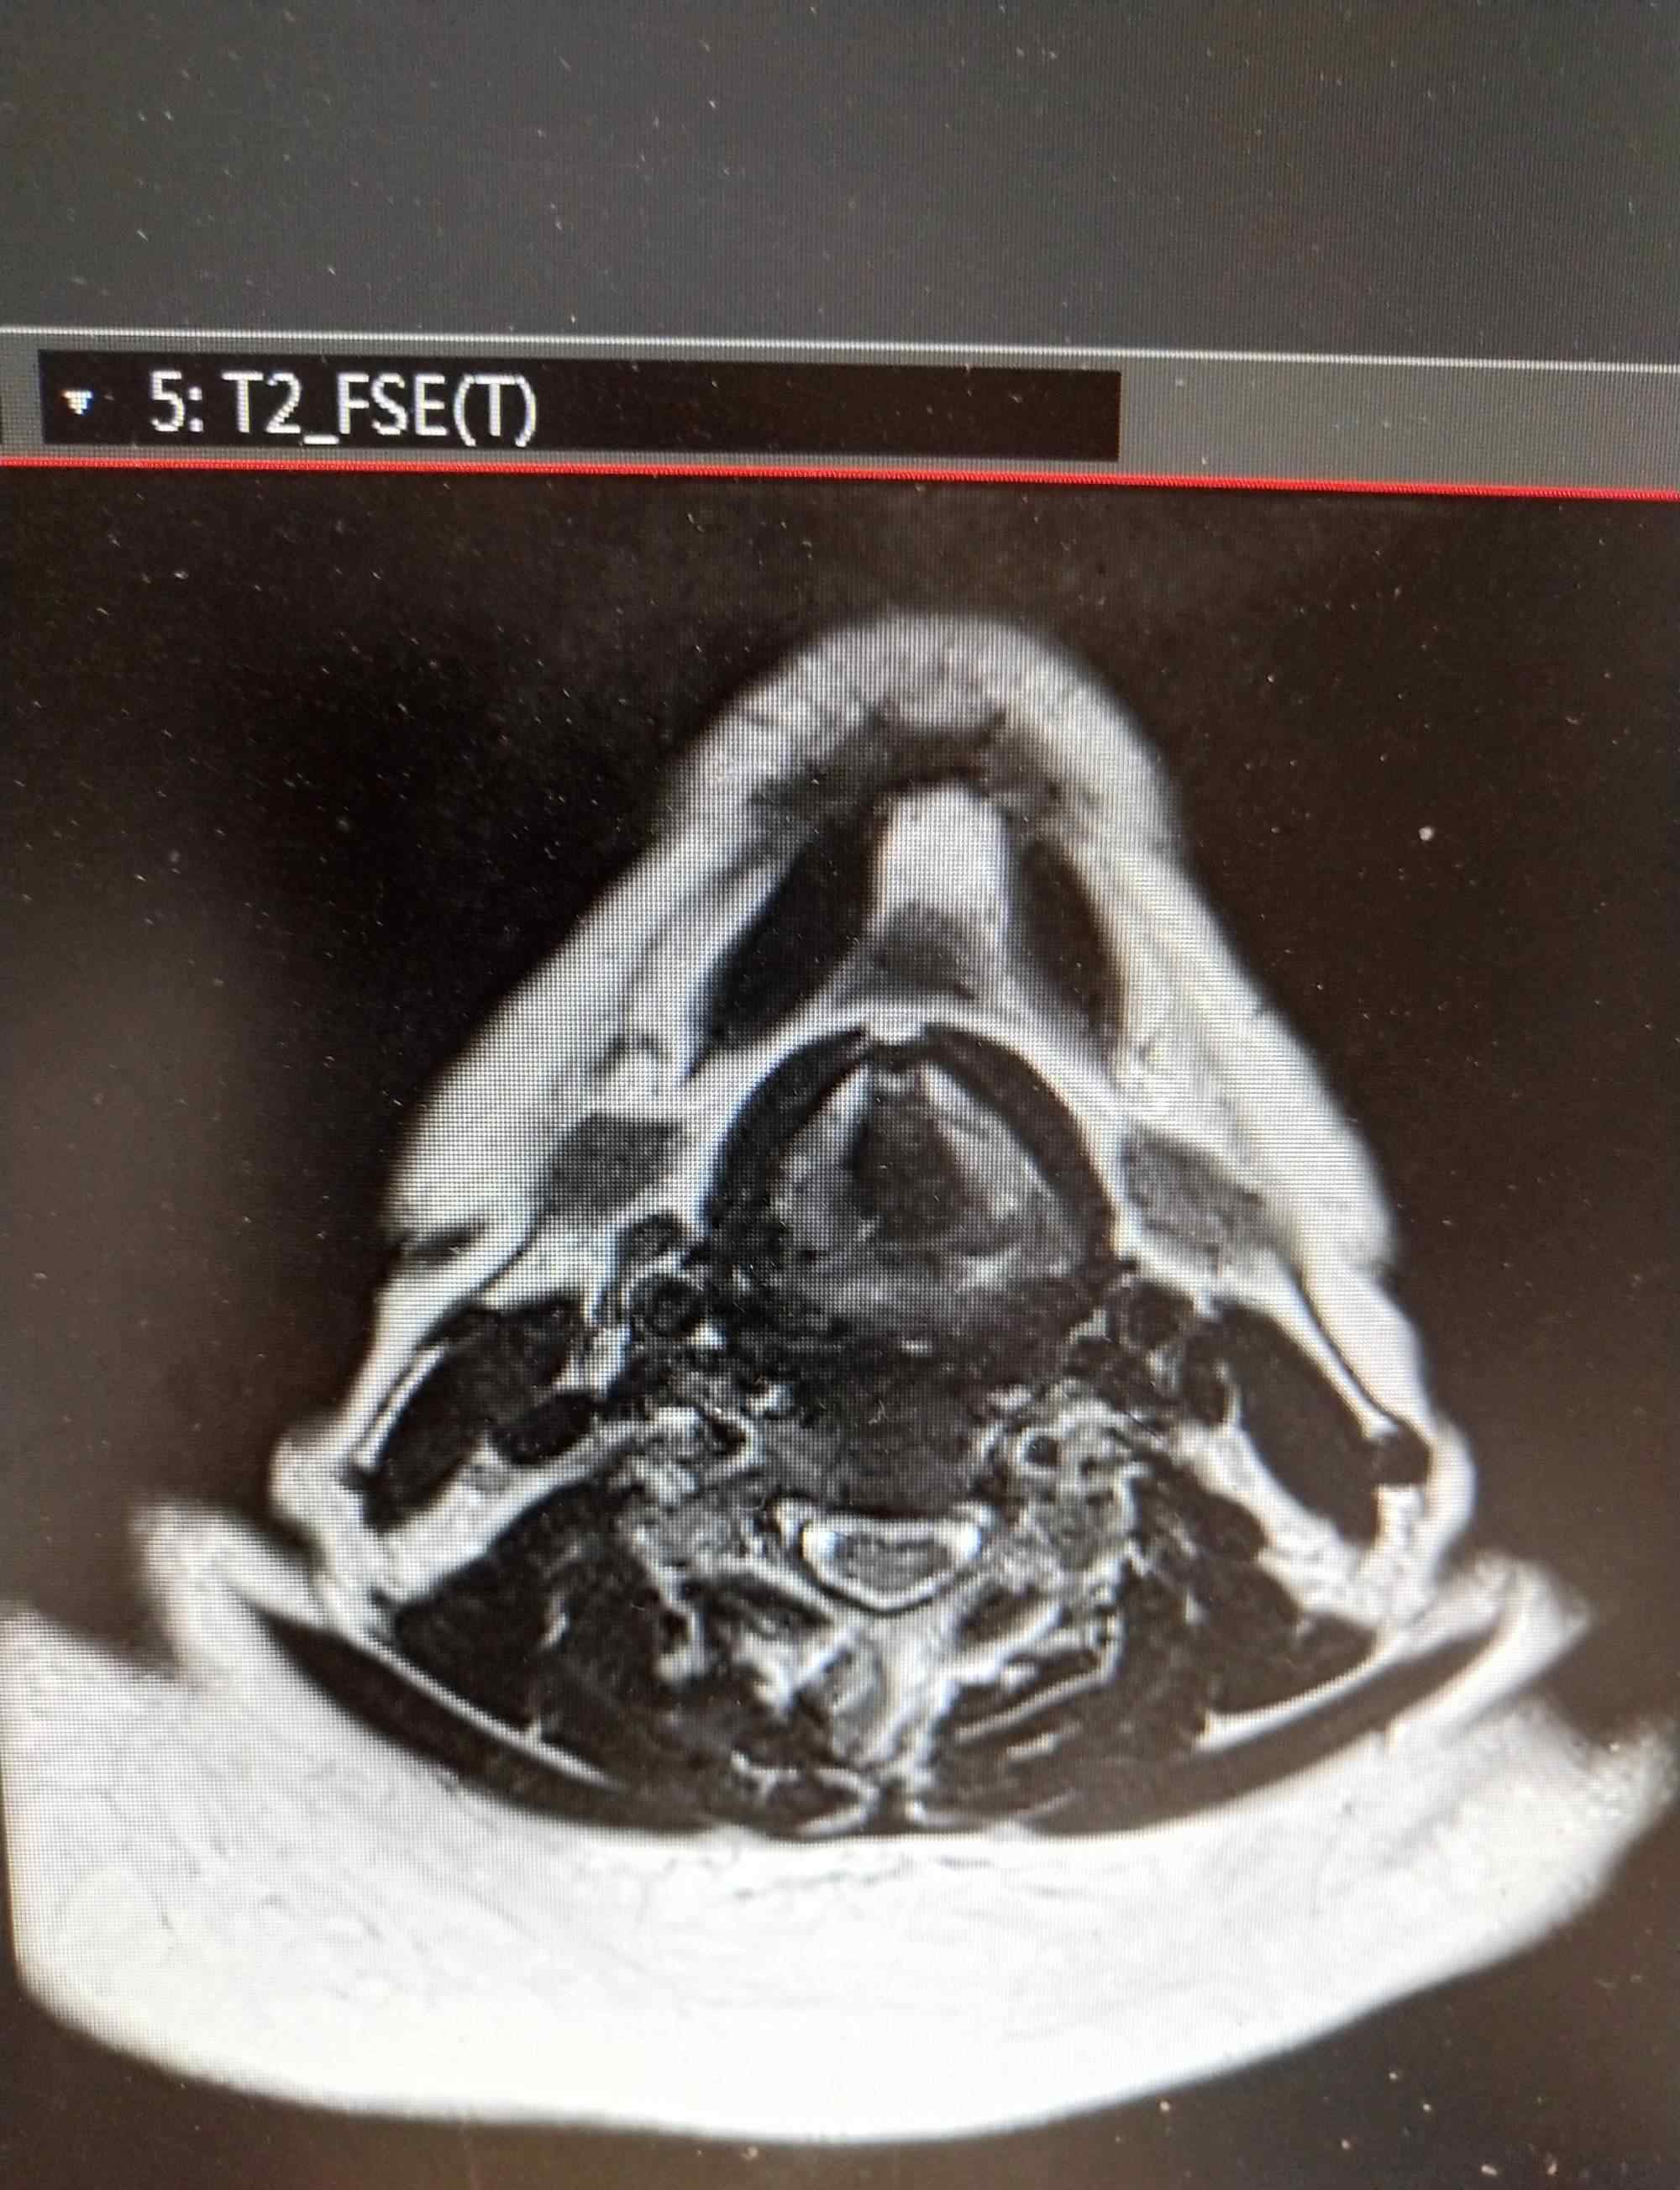

MRI